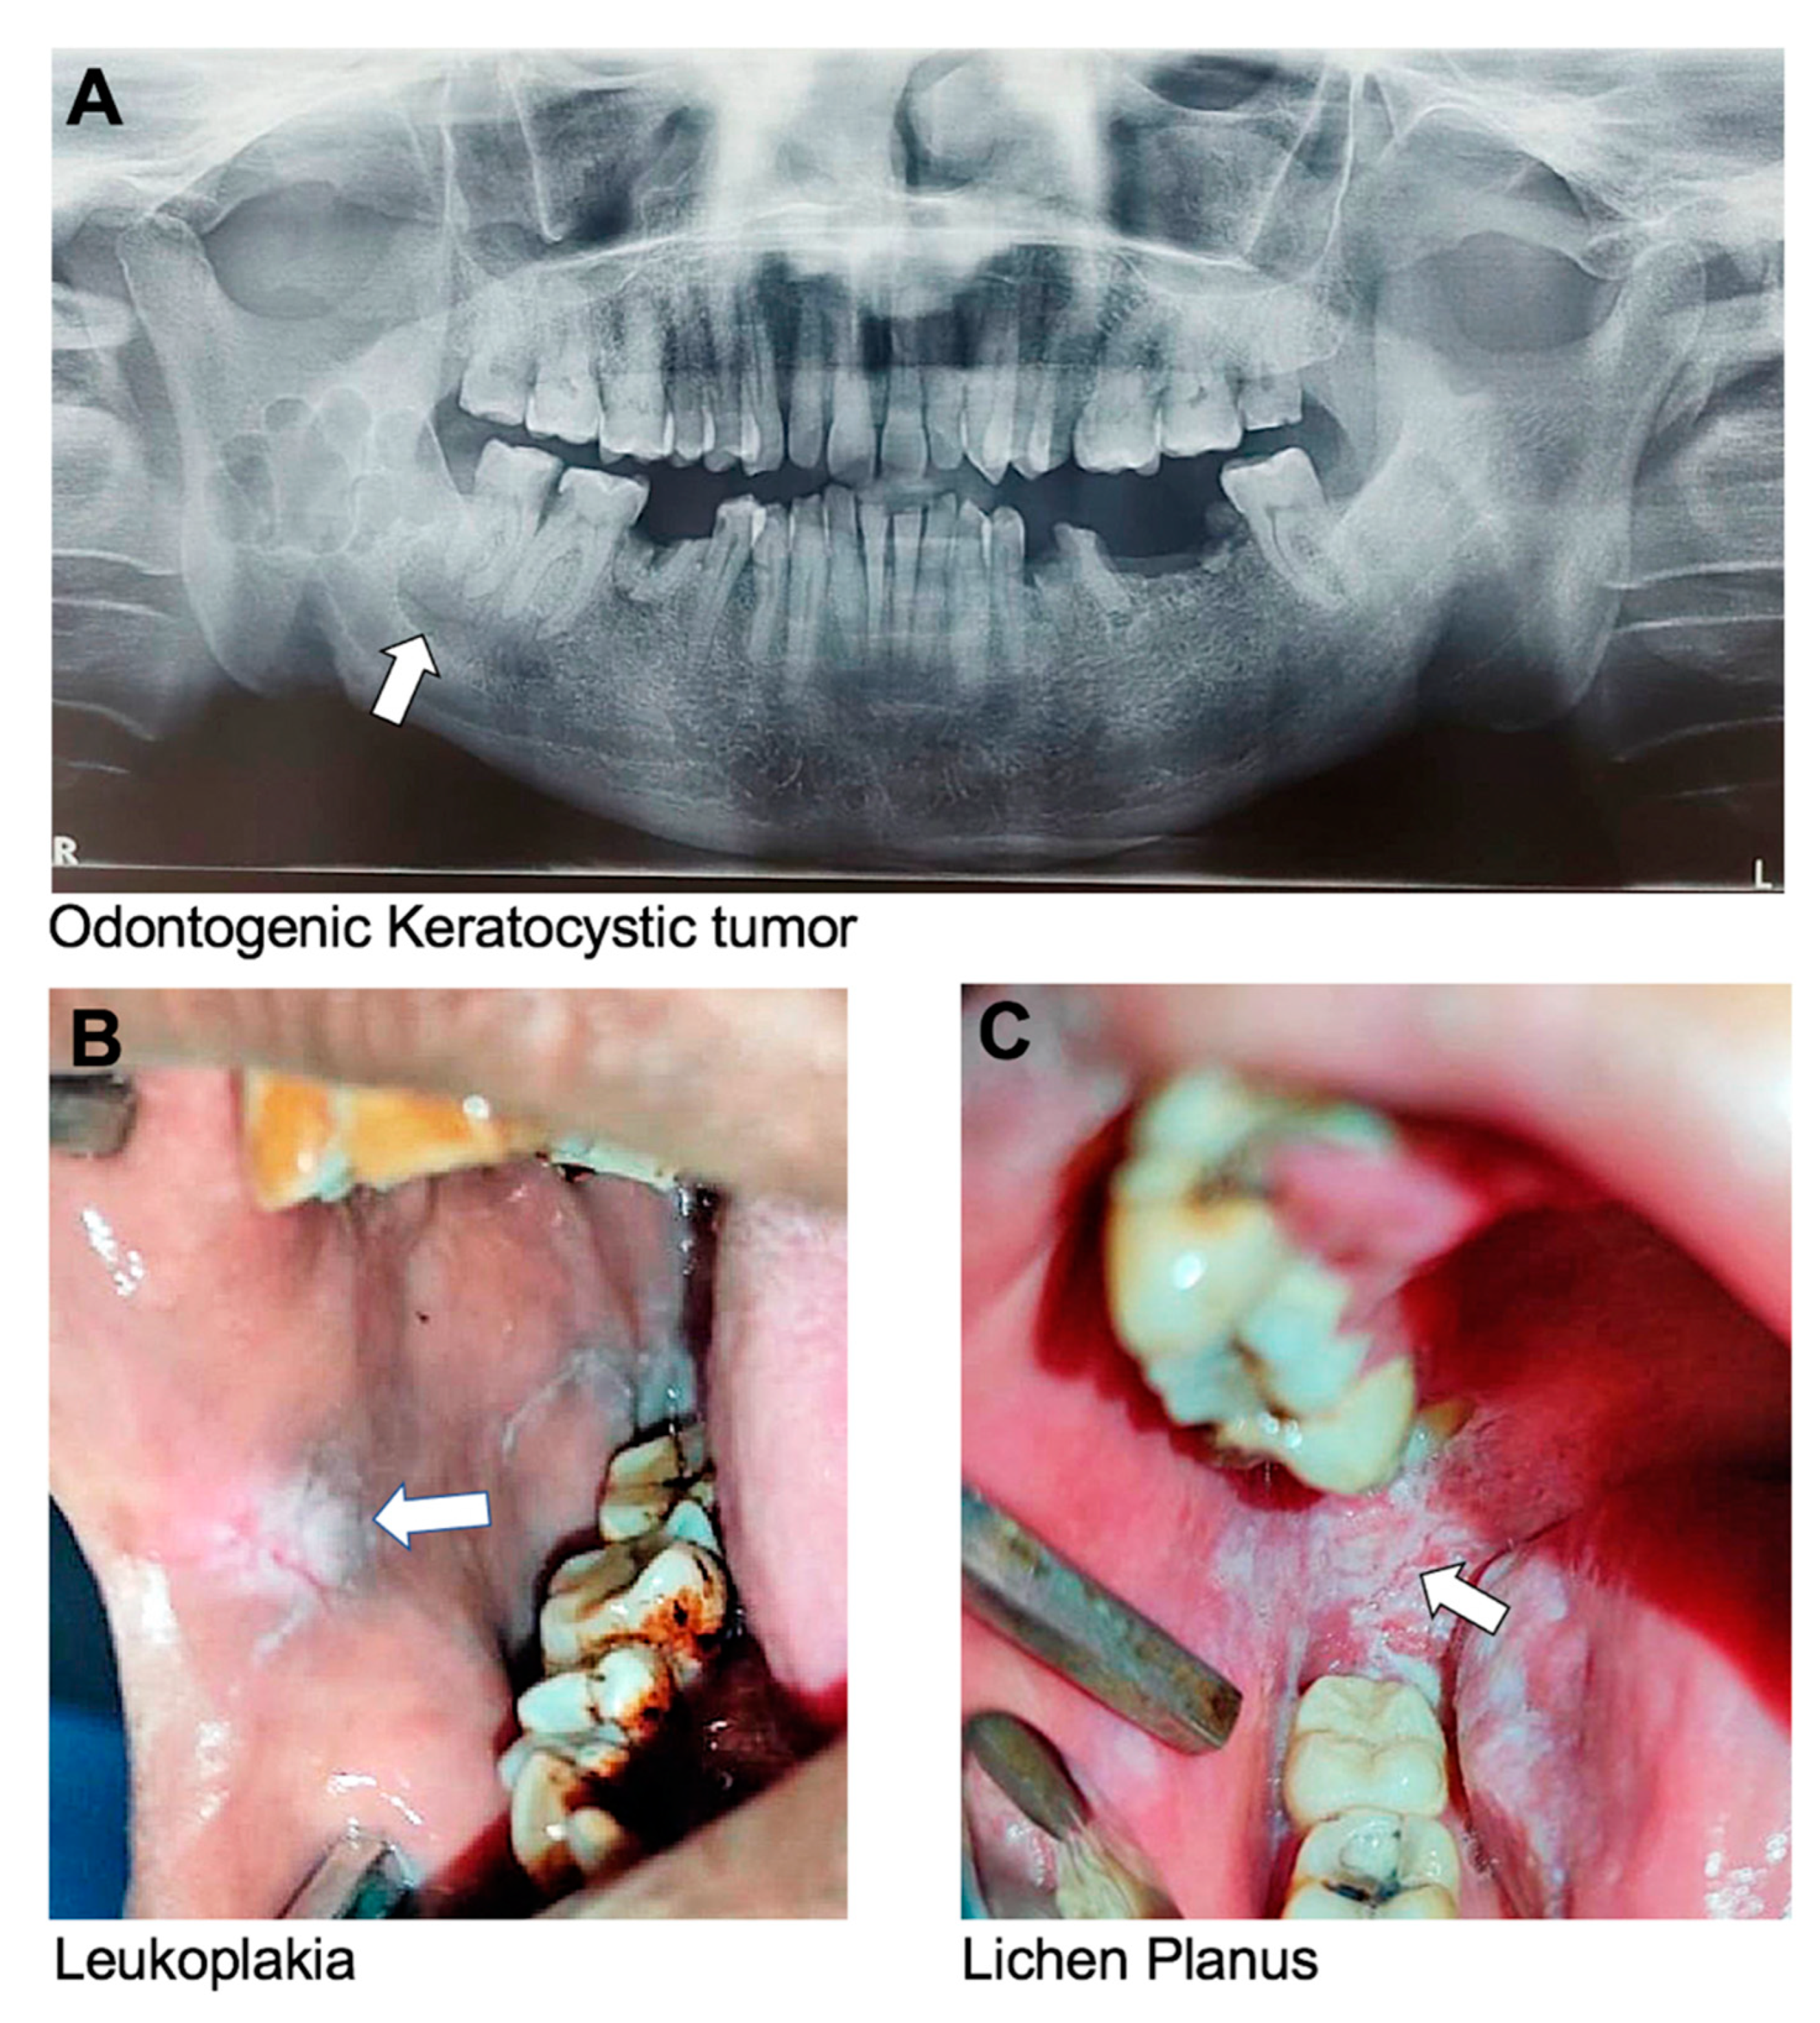

Keratocystic Odontogenic Tumor (KCOT):

Previously known as an odontogenic keratocyst, a KCOT is a benign but locally aggressive cystic tumor that originates from the epithelial cells of the dental lamina. It most commonly affects the mandible and can cause bone destruction if left untreated (Figure 3A). In some cases, genetic testing may be recommended for individuals with multiple or recurrent KCOTs, as there is an association with a genetic disorder called nevoid basal cell carcinoma syndrome [106]. A few studies have associated mutations in PTCH with KCOT [122,130,131].

Leukoplakia

Leukoplakia is a potentially malignant lesion characterized by white or grayish patches having a mud-crack-like appearance that cannot be scraped off. It forms on the mucous membranes of the mouth, including the tongue, buccal mucosa, and gingiva. The patches are typically thick, raised, and have a rough or scaly texture (Figure 3B) [132]. Leukoplakia is usually painless but may be sensitive to touch or hot, spicy foods. The exact cause of leukoplakia is unknown, but it is believed to be associated with irritants such as tobacco use, alcohol use, and certain viral infections. Long-term use of tobacco is the most common cause of leukoplakia, particularly in the form of chewing tobacco or snuff. Heavy alcohol consumption may also increase the risk of developing leukoplakia, especially when combined with tobacco use. Despite being a possibly malignant disease, the total malignant development of oral leukoplakia is on the order of 5% or higher [133].

Oral Lichen Planus

Oral lichen planus is a chronic inflammatory condition that affects the oral mucous membrane. Lichen planus can also affect the skin, nails, and hair. Oral lichen planus is characterized by the appearance of white, lacy patches on the labial and buccal mucosa, gingiva, and tongue (Figure 3C) [136,137]. These patches may be painful or cause a burning sensation, particularly when eating or drinking acidic or spicy foods. In more severe cases, oral lichen planus may cause blistering, ulceration, or thickening of the oral mucosa. Oral lichen planus is considered to be an autoimmune condition. Certain medications, such as nonsteroidal anti-inflammatory drugs (NSAIDs), may also contribute to the development of oral lichen planus [138].